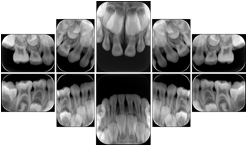

2. A patient requests cosmetic surgery to enhance their facial appearance. The case requires consultation between an orthodontist in New York and an oral surgeon in California. The cephalometric series of 2D projections constructed from a volumetric CT data set that is used for the discussion is arranged by a Structured Display for transfer between the two practitioners.

Cephalometric Series Structured Display

Figure OO-2. Cephalometric Series Structured Display